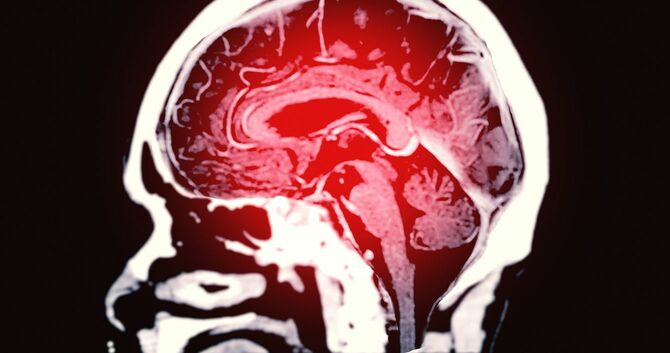

2018年1月のある日の深夜、脳卒中により左脳の深部血管が破れ、ドス黒い血が脳の3分の1を覆った妻(43歳)の手術は約7時間に及んだ。

その間、設楽完事さん(仮名・50代)は、術前に見せてもらったCT画像を思い出しては、「もう戻ることはないだろうな」と諦めてみたり、「助かってほしい」と願ったり、「妻が望まぬ形ならいっそ助からないでほしい」と考えたりしながら、寒くて狭い控え室で一度も座ることなく、ひたすら歩き回っていた。